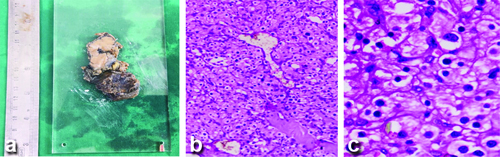

A 43-year-old male with no history of any co-morbidities came to the OPD with complaints of an anterior neck swelling of eight years’ duration. On examination, a firm nodule of size around 3×3 cm was noted in the left lobe of the thyroid gland. USG of the neck showed a well-defined heterogeneous nodule at the isthmus reaching upto the left lobe of the thyroid with prominent vascularity on colour Doppler. CECT showed an intensely homogeneous enhancing mass with an irregular outline involving the left lobe and isthmus. The lesion is noted to extend to the left anterolateral aspect of the trachea and anteriorly infiltrating the strap muscles, with radiological features suggestive of malignancy. The patient was referred to the Surgical Oncology Department. Imaging-guided FNAC smears showed cellular smears suggestive of a follicular neoplasm. The patient underwent total thyroidectomy with central compartment node dissection and partial tracheal resection (first and second ring). Intraoperatively, the airway was secured initially with endotracheal intubation, and after post-tracheal resection, the patient was tracheostomised. Histopathological examination {Haematoxylin and Eosin (H&E)} showed a tumour composed of sheets and nests of polygonal cells with eosinophilic cytoplasm and deep-staining nuclei, with foci showing a Zellballen appearance. A differential diagnosis of parathyroid carcinoma/paraganglioma was suggested with invasion of the tracheal rings and strap muscles. All the level VI nodes were negative for metastasis. In immunohistochemistry, tumour cells were positive for synaptophysin, chromogranin, vimentin, GATA 3, and S100, and negative for Cytokeratin (CK), Thyroid Transcription Factor 1 (TTF1), Calcitonin, CAM 5.2, thyroglobulin, and PAX 8. The Ki proliferation index was 4-5%. A diagnosis of paraganglioma of the thyroid gland was made [Table/Fig-2a-c]. Postoperative whole-body Fluorodeoxyglucose-18 (FDG) Positron Emission Tomography (PET) showed no evidence of metabolically active FDG-avid disease anywhere else, suggestive of no distant metastasis. The patient is on regular follow-up with 75 mcg of oral thyroxine/day supplementation.

a) Gross cut surface specimen of the thyroid paraganglioma; b) Histopathology section showing round, polygonal cells arranged in nests (Zellballen pattern, H&E, 100X); c) Cells showing round to ovoid nuclei with eosinophilic cytoplasm (H&E, 400X).